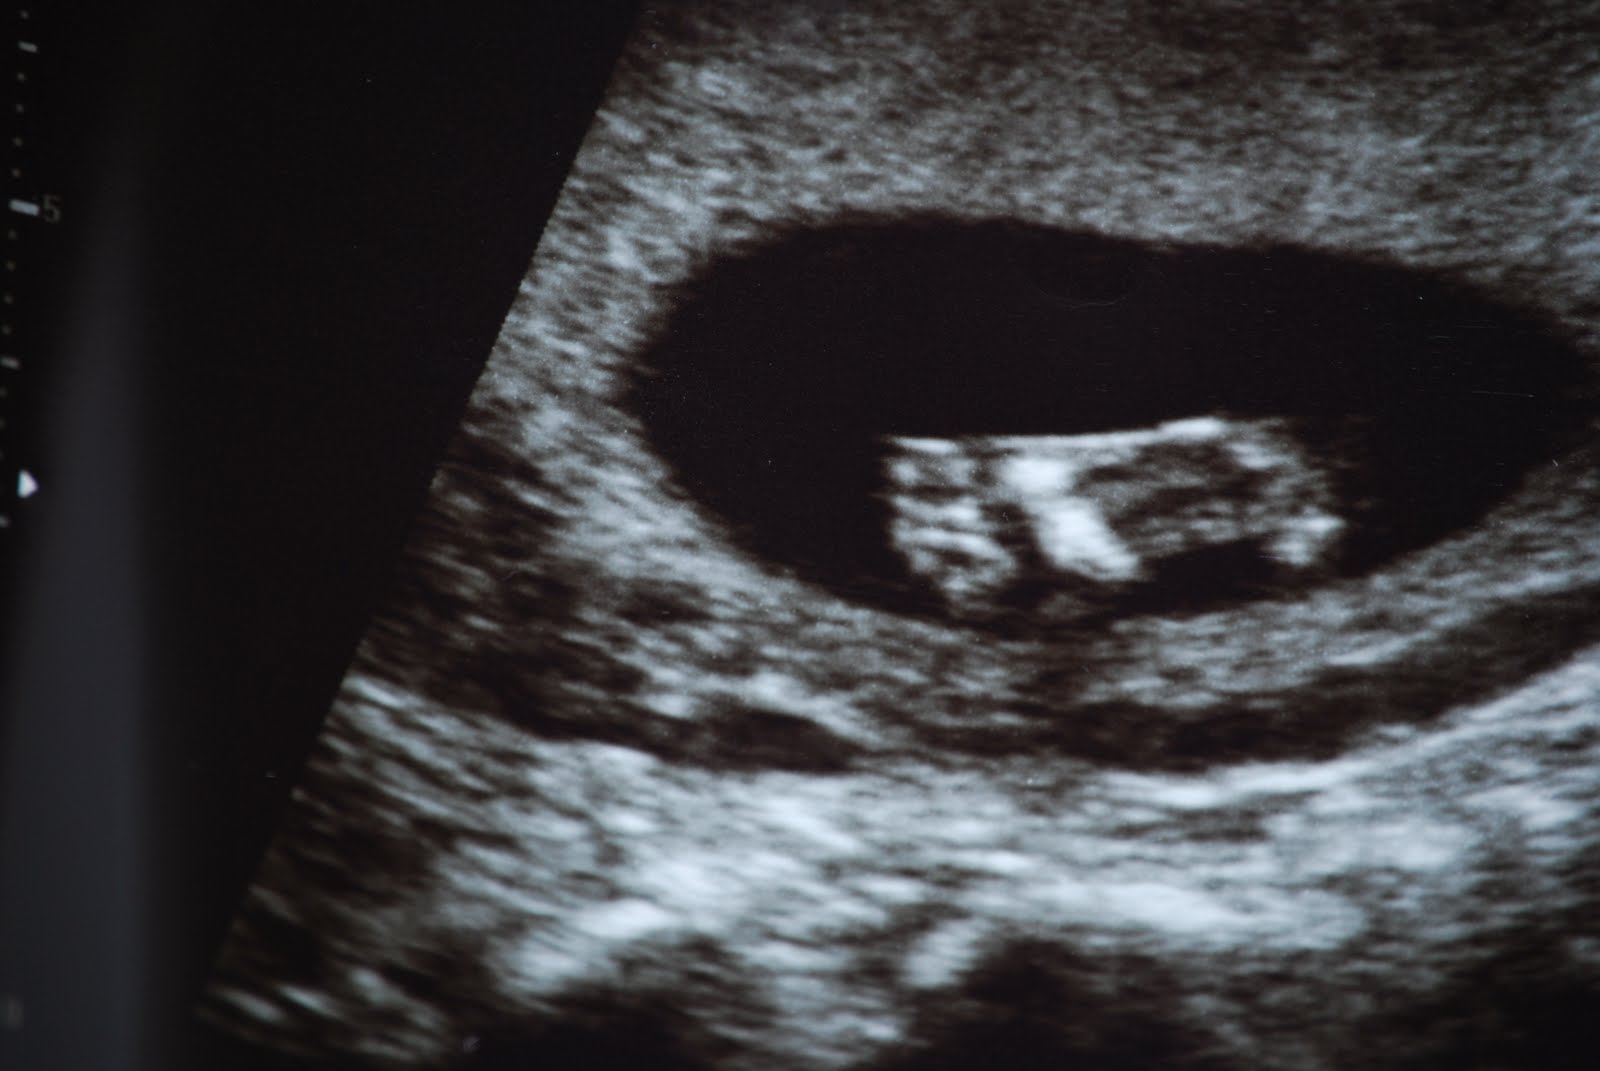

So we had our appointment with the Neonatologist today. The baby is 18 weeks and thus far is doing great. We got to see lots of pictures of our new addition, but the hitchhiker was not very cooperative today. we will be going back for another ultra sound in 4 weeks! They COULD have told us the gender, but we decided NOT to find out. It was SOOO hard to walk out the building not knowing if it is a girl or a boy! Here is the Hitchhiker's photo shoot!

The Hitchhiker!

The profile!